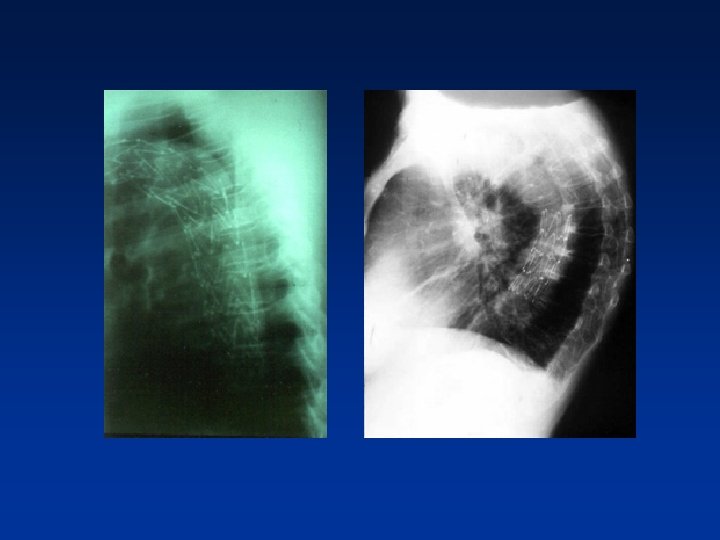

Doenças da aorta torácica • Dissecção aguda da aorta(tipo B) • Dissecção crônica da aorta • Hematoma intramural • Aneurisma verdadeiro • Pseudoaneurisma

Tratamento Endovascular

Endoprótese Torácica E. Saadi/2008

Aneurisma Aorta Torácica e Dissecção de Aorta • • • • Cirurgia dealto altíssimo Cirurgia de risco Mortalidade 20%% Mortalidade 55 - -20 Morbidade(complicações): -- paraplegia: : 55 -- 20 20% % -- AVC 10 a 20 dias de hospitalização, -5 Amputação de M. Inferiores a 7 dias em UTI 10 20 CEC dias de hospitalização, 5 Usoade a 7 dias em UTI Obrigatório o uso de CEC

Avaliação Pós-Procedimento Acompanhamento com TC de Múltiplos detectores ou eco TE 30 dias após procedimento e 1 x/ano - Vazamentos(endoleaks) - Expansão do falso lúmen ou aumento do aneurisma - Migração ou falha estrutural da endoprótese